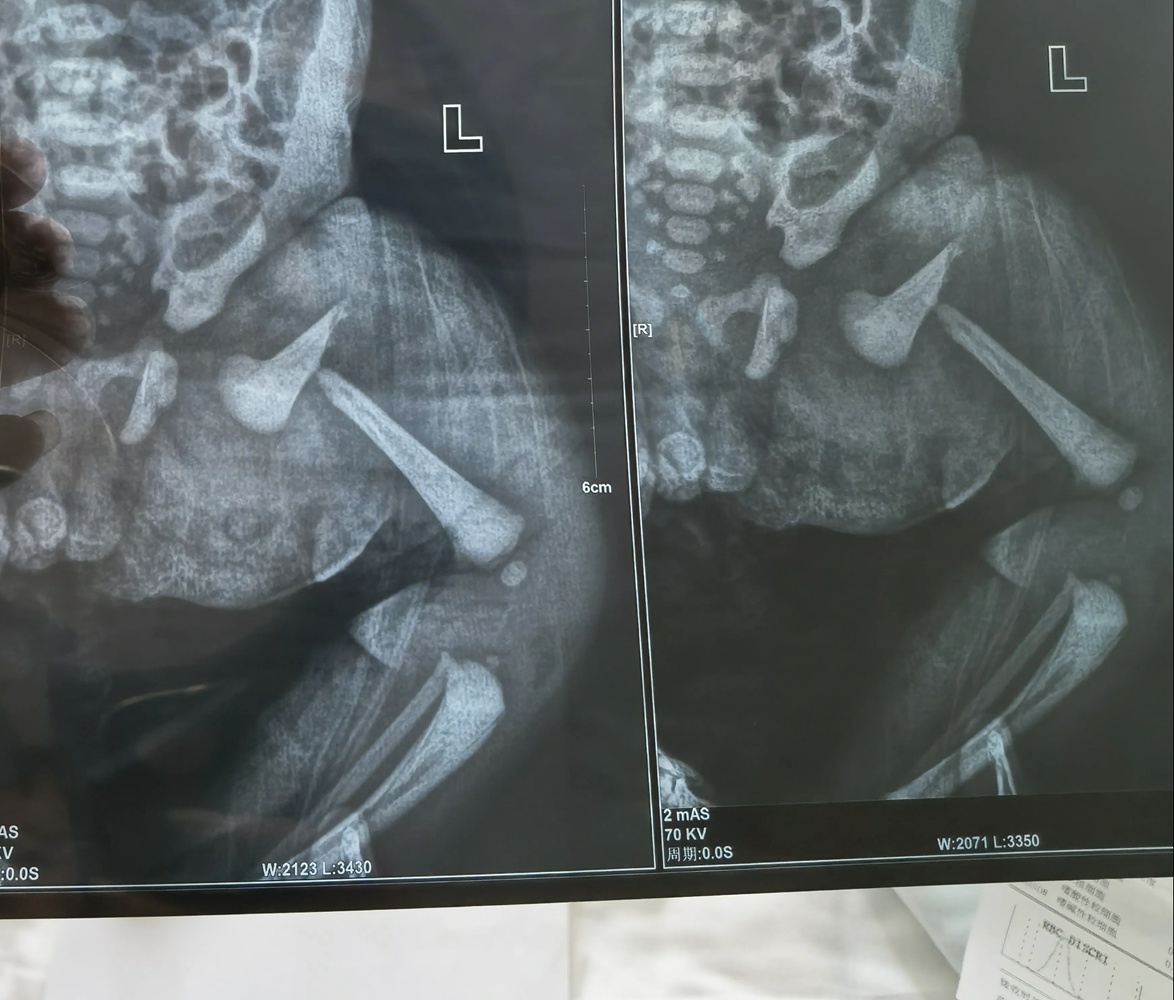

河南信阳的王女士告诉九派新闻,其在潢川县人民医院进行了剖宫产术。40小时后,她发现孩子不停哭闹、大腿肿胀严重。通过X光检查,婴儿左腿股骨干呈90度断裂状态。

X光显示,婴儿左腿股骨干骨折。图/受访者提供